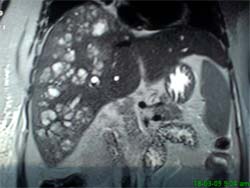

Các nhà nghiên cứu Lim JH, Mairiang E, Ahn GH đang công tác tại khoa chẩn đoán hình ảnh, Trung tâm nghiên cứu y học Samsung Medical Center, đại học y khoa Sungkyunkwan, Seoul, Hàn Quốc, đã tiến hành một nghiên cứu tổng thể về các bệnh ở đường mật do ký sinh trùng: sán lá gan lớn và sán lá gan nhỏ (Clonorchis sinensis, Opisthorchis viverrini). Các sán này nằm trong các đường mật nhỏ ngoại vi của gan và có thể dẫn đến hâuu quả viêm nhiễm mạn tính, dãn đường mật, tắc nghẽn cơ học đường mật và dày thành ống mật. Về hình ảnh học, các đường mật ngoại vi nhỏ bị dãn nhưng các đường mật lớn và ngoài gan không dãn hoặc dãn rất nhẹ. Không thấy tắc nghẽn đường mật. Đôi khi, nhiễm trùng nặng, các sán trưởng thành có thể thấy được qua siêu âm, CT hoặc MRI đường mật và hệ gan mật và có thể thấy các tổn thương nhỏ trong gan mật đi kèm. Những con sán trong túi mật có thể trôi nổi trong túi mật, các vật thể nhỏ này thấy qua siêu âm. Nhiễm mạn tính có thể dẫn đến bệnh lý ung thư biểu mô đường mật trong nhu mô gan và đường mật. Nhiễm sán lá gan lớn ở người loại Fasciola hepatica, có thể xảy ra tình cờ, sán di chuyển trong nhu mô gan (pha cấp) hoặc pha mạn trong đường mật. Chẩn đoán hình ảnh trong pha gan là các hình ảnh ổ áp xe li ti, đa ổ và hoại tử lớn nhỏ khác nhau, dạng đường hầm hoặc khoang, chứng minh có ký sinh trùng di chuyển trong nhu mô gan. Trong pha đường mật (mạn tính), sán có thể nằm trong đường mật trong và ngoài gan hoặc túi mật, dưới dạng các vật thể trôi nổi và dãn đường kính.